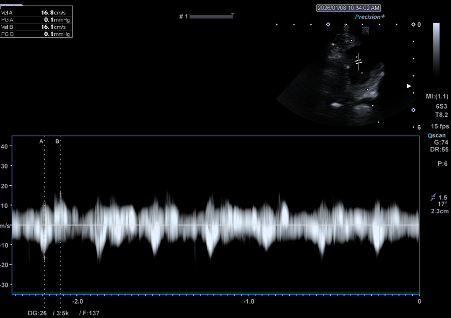

좌심방이 혈류 속도 측정 결과

- Filling velocity: 16.1 cm/s

- Emptying velocity: 16.8 cm/s (정상 ≤28 cm/s)

→ 혈액이 좌심방이에 오래 머무르는 뚜렷한 혈류 저하가 확인되었습니다.

환자의 심장초음파 사진(좌심이 혈류 속도 filling velocity 16.1cm/s, emptying 16.8cm/s 두드러진 감소 (정상 28cm/s 이내)) / 출처: 24시 동탄리더스동물의료원